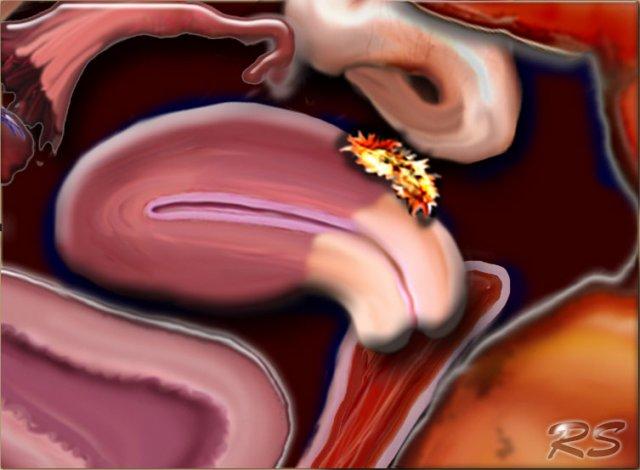

Hình minh họa cho thấy các vị trí điển hình của lạc nội mạc tử cung:

- Lạc nội mạc tử cung dạng u nang buồng trứng (endometrioma)

- Lạc nội mạc tử cung sau cổ tử cung

- Lạc nội mạc tử cung xâm lấn sâu vào ruột

- Lạc nội mạc tử cung tại bàng quang

- Lạc nội mạc tử cung tại thành bụng